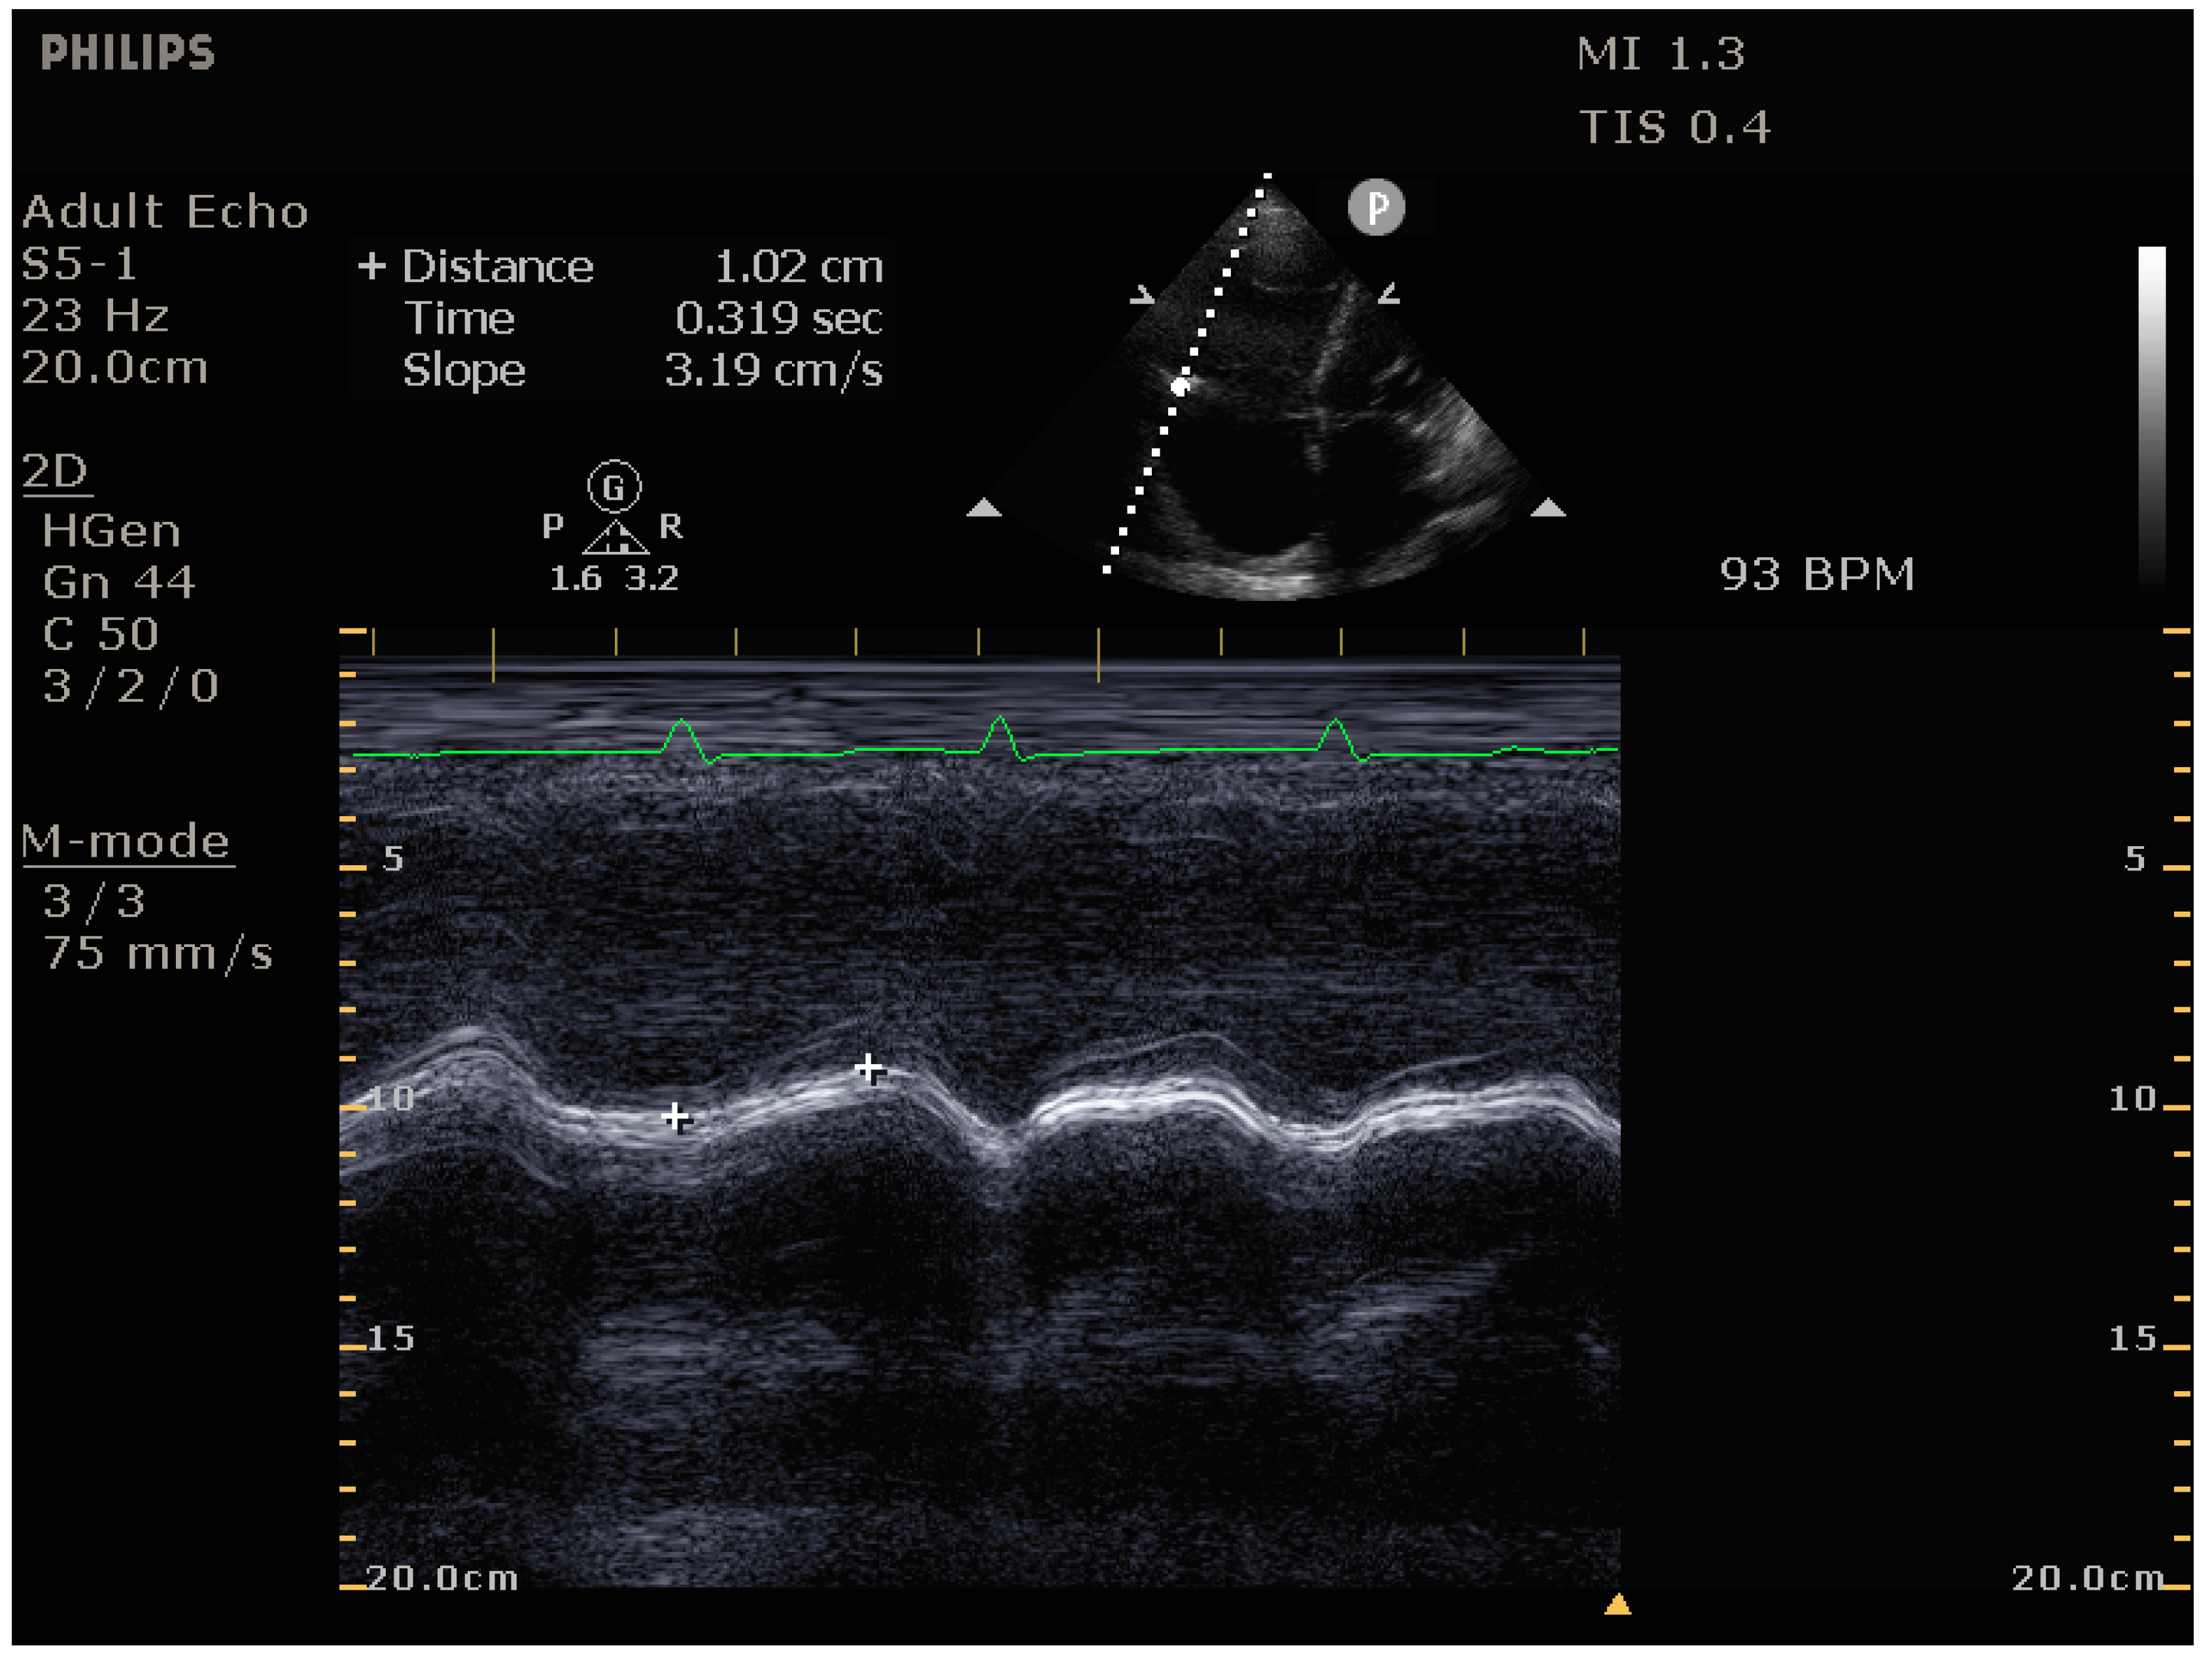

4.2.2. Echocardiography

- Signs of impaired RV systolic function: reduced tricuspid annular plane systolic excursion (TAPSE)